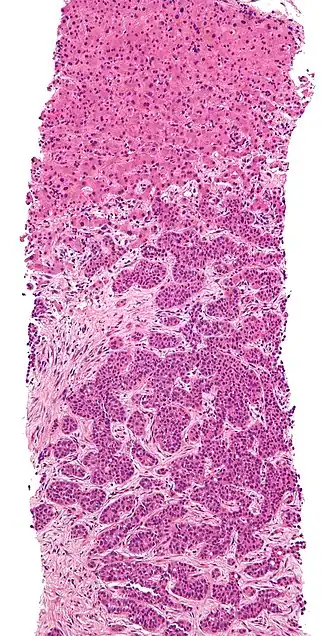

Het nemen van een leverbiopt is de enige manier om het leverweefsel direct te kunnen bekijken onder de microscoop. Voorafgaand aan een leverbiopt wordt de patiënt eerst lokaal verdoofd. Daarna wordt er met een holle naald tussen de ribben door in de lever geprikt om zo een klein pijpje leverweefsel te verkrijgen. Dit stukje leverweefsel wordt vervolgens door de patholoog bekeken. Hierbij kunnen de volgende aspecten worden onderscheiden: de mate van fibrose (verlittekening) van het leverweefsel, de mate van ontsteking, de opbouw van het leverweefsel en bepaalde specifieke kleuringen kunnen gedaan worden.

Een van de belangrijkste dingen om naar te kijken in een leverbiopt is de hoeveelheid fibrose. Fibrose is littekenweefsel dat in de lever ontstaat doordat er gedurende een heel lange tijd (jaren) ontsteking in het leverweefsel aanwezig is. Er zijn verschillende manieren om aan de te geven hoeveel fibrose er in de lever zit. Een van de meest gebruikte methodes is de Metavir-classificatie. Hierbij wordt de hoeveelheid fibrose ingedeeld in 5 groepen, F0 t/m 4. F0 is geen fibrose, F1 is minimale fibrose, F2 is matige fibrose, F3 is ernstige fibrose en F4 is cirrose.